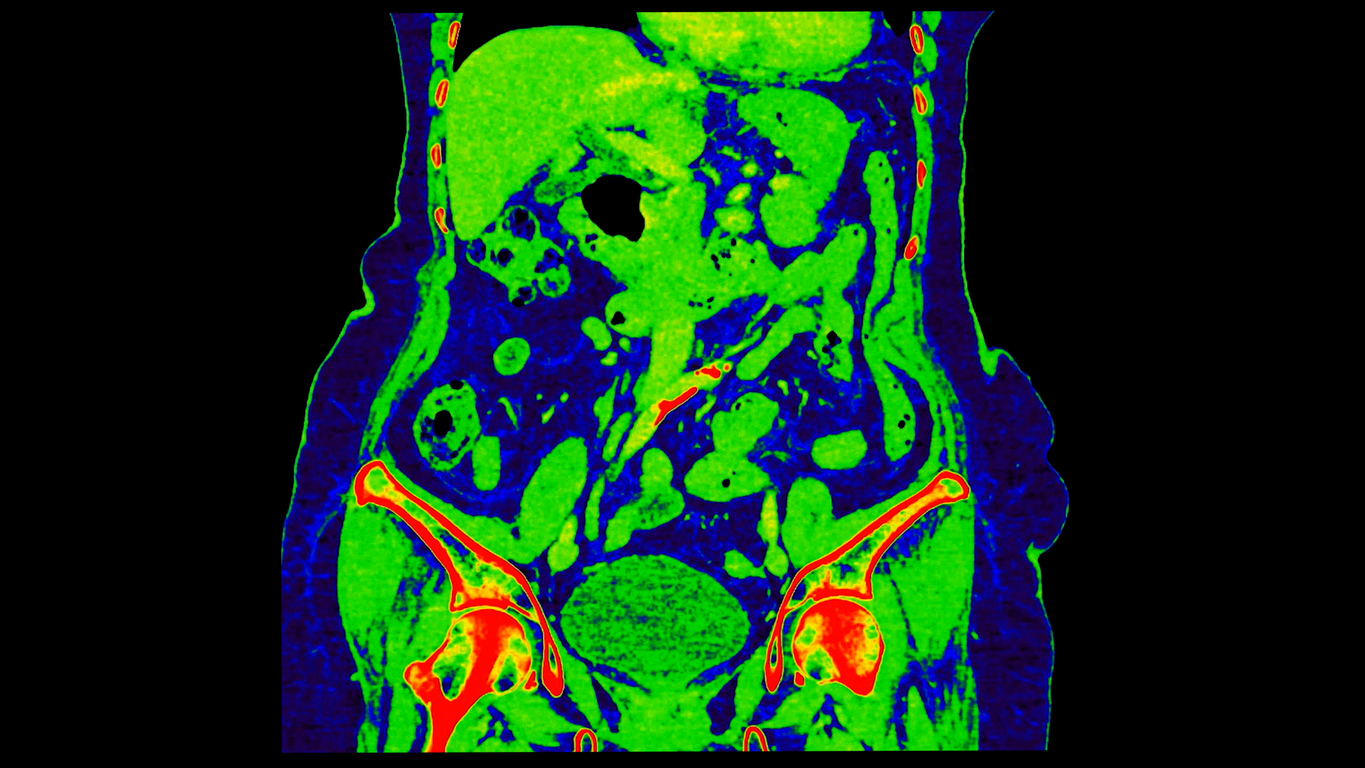

I completed a residency in emergency medicine in 1984, when it was a brand-new specialty. There is probably no other specialty that is so focused on the art of diagnosis. Frequently, the emergency physician must evaluate a patient with abdominal pain. In the days when CT scanning was confined to the skull, a very detailed history and physical examination and a lot of experience and judgment were required to differentiate appendicitis from diverticulitis and to correctly diagnose the rapidly fatal aortic aneurysm when the majority of patients with that sort of pain were suffering from a kidney stone or something else which wasn’t immediately life-threatening.

In the early 1990s, the small hospital where I worked acquired a CT scanner capable of scanning the abdomen and chest. In the Emergency Department, we seldom ordered a CT scan of the abdomen because we had developed expertise in diagnosing without relying on advanced imaging. In addition, we knew that the radiologist would complain bitterly about the “inappropriate” overuse of CT scans when they were not necessary. Interestingly, the medical necessity for a CT scan was even harder to justify after 5 PM on weekdays and weekends. However, as the scanners became faster, physicians gradually came to depend more on CT scans for patients with suspected intra-abdominal pathology.

Ultimately, CT scanning revolutionized clinical practice worldwide, and the United States adopted it with particular enthusiasm. In 1983, American providers performed an estimated 5.5 million CT procedures. By 1995, that number had surged to approximately 20 million. By 2011, CT use in the United States far outpaced that of other OECD nations, with 273.8 scans performed annually for every 1,000 people—more than twice the 16-country average of 121.7 per 1,000.